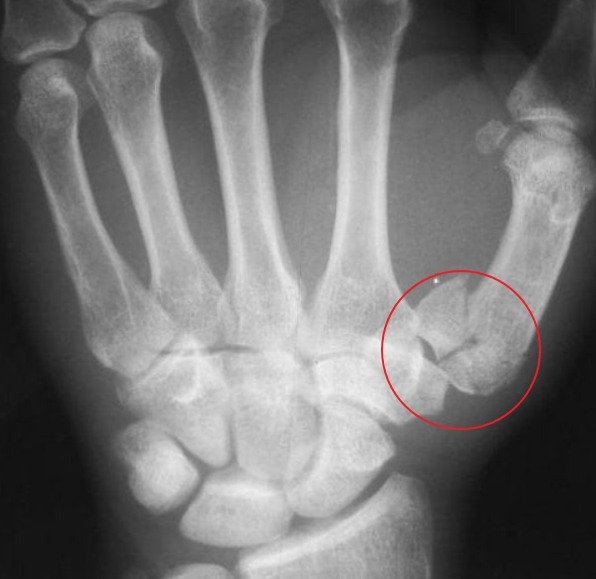

- 역 Bennet 골절 : 제5 중수골 기저부 관절 내 골절. 무지에서와 같이 외측 근위부로 전위가 발생합니다. 전위가 없으면 3~4주간 고정하여 치료될 수 있으나 대개 도수 정복 후 K-강선 고정 또는 관혈적 정복술로 수술적 치료합니다.